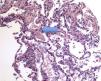

Proteinosis alveolar en un paciente inmunocompetente con infecciones previas por Legionella y Nocardia

Alveolar proteinosis in an immunocompetent patient with previous Legionella and Nocardia infections